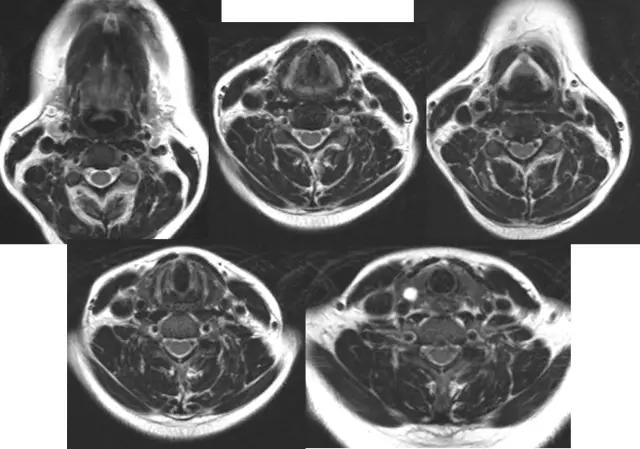

2、CT

1、常规采用横断面扫描,喉腔中轴与扫描线垂直;

2、扫描范围自环状软骨下缘至下颌角会厌上缘,层厚3-5mm;

3、发音状态扫描:让病人连续发“E“音,这时声带内收,可较好显示声带、梨状窝、咽后壁及杓会厌壁的形态及病变。

2、CT、MRI检查

喉软骨:软骨骨化及髓腔形成的程度。

1、年轻人软骨未骨化,T1及T2WI等信号,CT等密度,与其它软组织较难区分。

2、30岁以上成年人T1WI中央高信号代表脂肪及黄骨髓生成。年老时骨化变为皮质骨,信号减低。CT为高密度。

3、会厌软骨由弹性软骨组成,T1WI略低于肌肉,T2WI略高于肌肉。CT呈等密度,少有钙化。

正常喉部CT